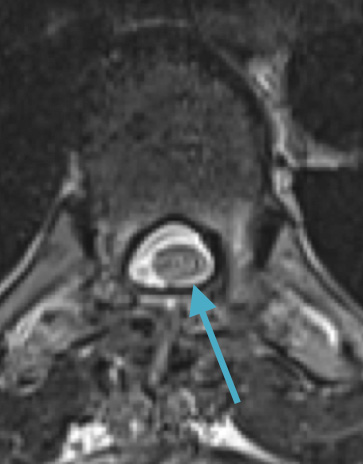

Preoperative MRI T2 demonstrating obstruction of CSF around the cord (blue arrow), resulting from the tumor (red arrow)

Preoperative MRI T1w demonstrating a large enhancing tumor with severe cord compression